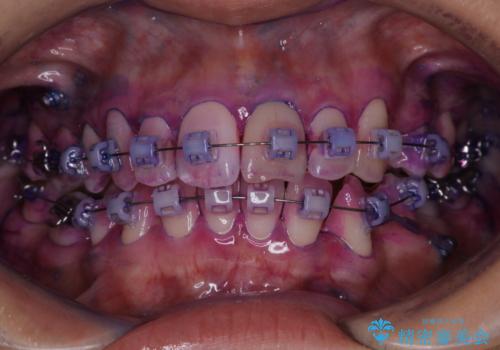

- ワイヤー矯正中に、口臭や汚れが気になり綺麗にクリーニングしたいとのことでした。染め出しをしての歯磨き指導とPMTC60分コースを行いました。

ワイヤー矯正中はブラッシングが難しくなるため、磨き残しが多くなることがあります。

ご自身でのブラッシングケアでは、歯周ポケットの中に歯ブラシの毛先が届くのはわずか2ミリ程です。軽度の歯周炎の場合でも歯周ポケットは3ミリほどあります。歯茎の中に長く汚れが溜まると、歯石や細菌などがつき、口臭の原因にもなります。

適切な道具を使って、適切なブラッシング方法を習得することで、磨き残しを減らすことができます。

また、矯正で歯の移動があると今までなかったところに隙間が出てきたり、ガタつきが解消されてきたりすることで、お口の中の環境が変わります。

矯正治療中も清潔な口腔内を保つことは、とても大切です。そのため、定期的に専門的な機械・材料を使用したProfessinnalcleaning(pmtc)を行うことがおススメです。